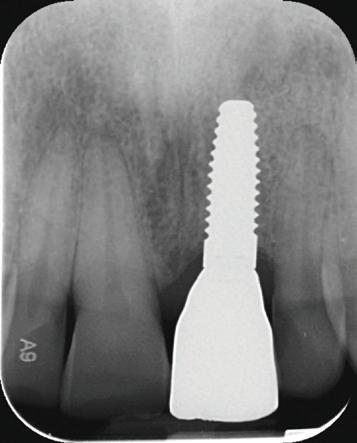

De asemenea, trebuie evaluate anual modificările radiografice. În ședința de inserție a restaurării, se înregistrează o radiografie bitewing standardizată pentru a permite evaluarea anuală a modificărilor osoase din jurul implantului. Remodelarea osului alveolar în primul an este bine documentată și depinde de tipul de implant utilizat; cu toate acestea, nu ar trebui să apară apical de primul filet al implantului. Prin urmare, este importantă abilitatea de a vizualiza filetele implantului pe radiografii. Modificările pierderii osoase de 2 mm sau mai mult după primul an reprezintă un semn de periimplantită. De îndată ce pierderea osoasă este recunoscută, pacientului trebuie să i se recomande terapia imediată pentru a opri procesul de boală.

Combinarea corectă a formei, caracteristicilor suprafeței și poziționării unui implant poate conduce la creșterea osului în zona conică inversată a acestuia, așa cum au demonstrat cercetările științifice și practica de zi cu zi.

Utilizarea platform-switch și-a dovedit eficiența în sistemele moderne de implanturi. Însă acum, zona conică inversată oferă mai mult spațiu și un suport mai bun de aderență pentru țesutul dur și moale decât formele cilindrice ale implanturilor, așa cum cum se poate vedea în imaginea următoare.

Suprafața microstructurată din zona conică inversată sprijină atașarea osului și a țesutului conjunctiv. Atunci când marginea acesteia este poziționată subcrestal, este recomandată utilizarea unui material de augmentare (xenogrefă sau os autolog) care poate preveni dezvoltarea țesutului moale în zona conică inversată și poate oferi suport pentru o mai bună osteointegrare.